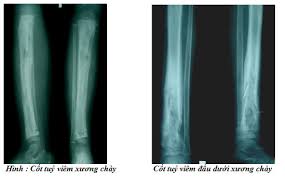

Click vào ảnh để xem 4 hình ảnh minh họa